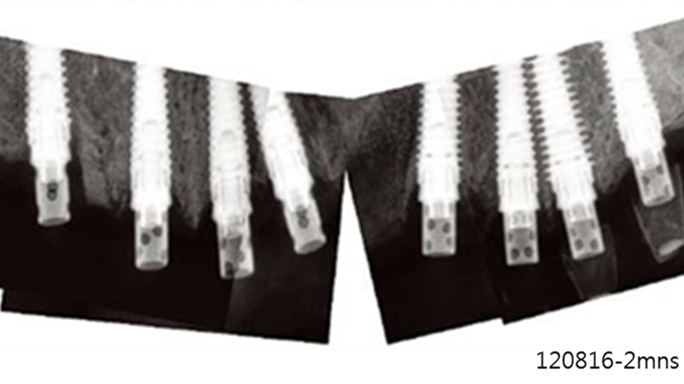

“AnyRidge shows excellent initial stability

& stable results after immediate loading in

upper fully edentulous case. ”

Clinical case: Extraction of all teeth in upper maxilla,

immediate implant placement, & provisionalization

- Courtesy of Dr. Iulian Filipov, Romania -